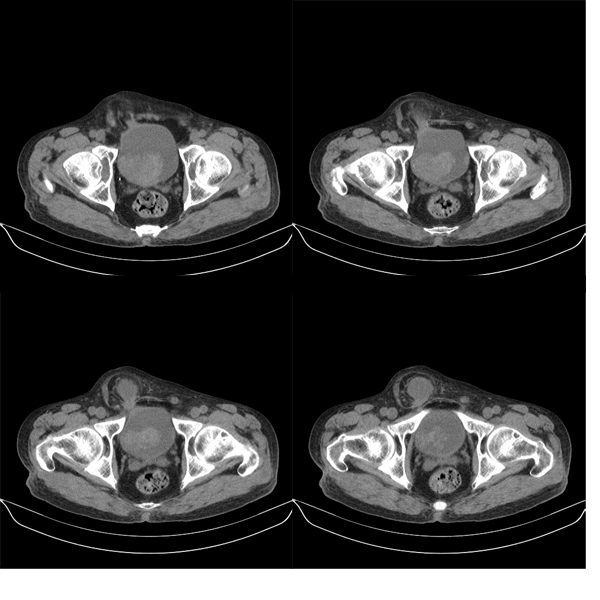

盆腔5mmct扫描

该病人年龄过大故放弃了增强.ct做完后本人检查病人发现病人耻骨联合上稍偏右见一突出的包块影,质地柔软,平卧位手压后可以回缩.站立位突出明显!

膀胱三角区右侧可见较大软组织肿块,分叶状,内可见更低密度区,ct做完后本人检查病人发现病人耻骨联合上稍偏右见一突出的包块影,质地柔软,平卧位手压后可以回缩.站立位突出明显!考虑腹股沟斜疝,疝内容物为膀胱.膀胱内肿物考虑1炎性赘生物2平滑肌肉瘤(有多年血尿史,本次加重且抗炎不好转)3膀胱癌

1.膀胱内软组织肿快,有点状钙化,前列腺不大.膀胱癌.

2.右侧腹股沟斜疝。

盆腔超级经典病例--膀胱癌+膀胱疝出引起的右侧腹股沟斜疝膀胱疝,果然名不虚传!谢谢楼主!   “m79y自述30年前做过疝手术,20年前间断出现尿血,每次经抗炎治疗后即好转”,这是因为膀胱的疝入甚至短暂或部分嵌顿以及由此引起的炎症所造成,当然抗炎治疗后好转;“近一月来又出现尿血但抗炎后仍尿血”,这就是膀胱癌在作怪了,呵呵。

1、右侧腹股沟斜疝,疝内容物为膀胱;2、膀胱右后壁肿块,考虑膀胱癌

可能是膀胱癌+滑疝